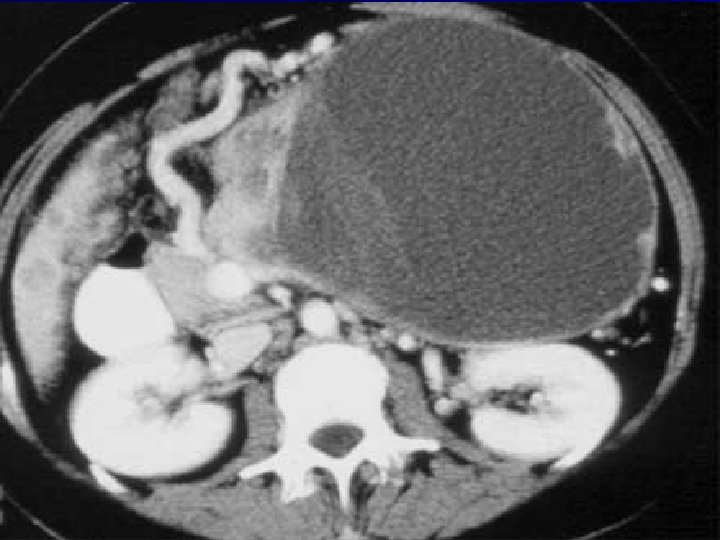

Apparition d’un pseudo -kyste du pancréas

Pseudo-kyste de la tête